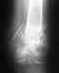

Подвывих копчика

Здравствуйте, 3 месяца назад ,не сильно упал вроде бы,но спустя месяц начали тревожить немного боли, обходил кучу травматологов у себя в городе, поехал в областную больницу. В итоге: хирург-проктолог сказал ,что копчик в ходячем состоянии, как после перелома ( но при переломе я бы вряд-ли смог ходить и сидеть, а такого не было), травматологи говорят разное : подвывих поставили диагноз, кто-то говорит загиб с рождения быть может и ничего точного никто не говорит, диагноз " травматическая кокцигодиния". Прикреплю снимки КТ и рентгена. Скажите есть ли что-то на снимках? Думаю пойти на отчаянный шаг, пойти к мануальному доктору, но смущает ,что вправляет без предв.снимка и анестезии. Боюсь сделать хуже